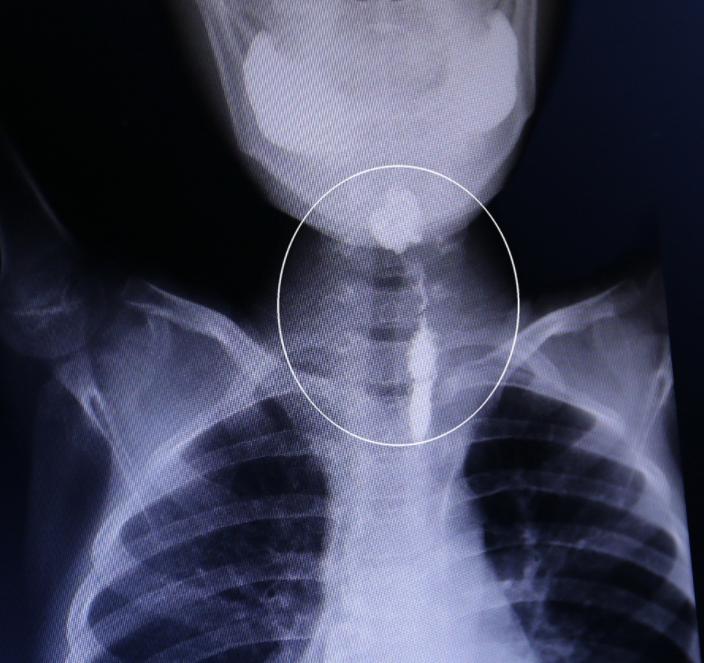

食管癌是指食管上皮的恶性肿瘤,是上消化道较常见的恶性肿瘤,目前已列为世界第八大癌症,食管癌早期一般无明显症状,有时吞咽粗糙食物时,可能会有不同程度的不适,如吞咽食物时呛咳、胸骨后灼烧、针刺瘙痒或拉痛。

中晚期患者的典型症状是进行性吞咽困难,晚期也难以吞咽水和唾液,患者体重逐渐减轻,脱水,身体虚弱,在晚期,可能出现持续的胸痛、背痛或声音嘶哑,吞咽水或食物时出现严重咳嗽,最后出现恶病质,如有肝、脑等器官转移,可出现黄疸、昏迷等症状。

接下来,让我们了解一下食道癌,食管癌是一种发生于食管的恶性肿瘤,占所有恶性肿瘤的2%,它一般分为三个阶段,即早期、中期和晚期,它发生在食管的上部、中部和下部,其症状通常为吞咽困难、吐血和其他症状。

当许多人感到这种不适时,他们总是觉得自己得了咽炎,这也是食管癌的早期阶段,从医学角度来看,咽炎和食管癌有一定的区别,一些食道癌患者在吃东西时会感觉到较强的异物,吞咽困难,所以面对这种情况,我们必须积极去医院检查。

早期食管癌的症状不明显,当吞下粗糙和坚硬的食物时,患者可能会受到食物对食管的拉动和摩擦以及胸骨后疼痛,它也可能由食道局部炎症引起的浅表溃疡引起,在中晚期,由于肿瘤侵犯食道外组织,患者将持续胸痛或背痛。

食管癌的临床症状之一是窒息,饮水或进食时,通过食管管腔进入胃的过程突然停顿,这与局部管腔狭窄导致的通道困难有关。

吃东西时,当你仔细体验时,你会感到窒息,表现为吞咽食物困难,食物落到某一部分时突然停顿,无法继续下降,这是食管癌最早的常见症状,当疾病晚期的肿瘤完全阻塞食管时,表明食物和水无法通过。